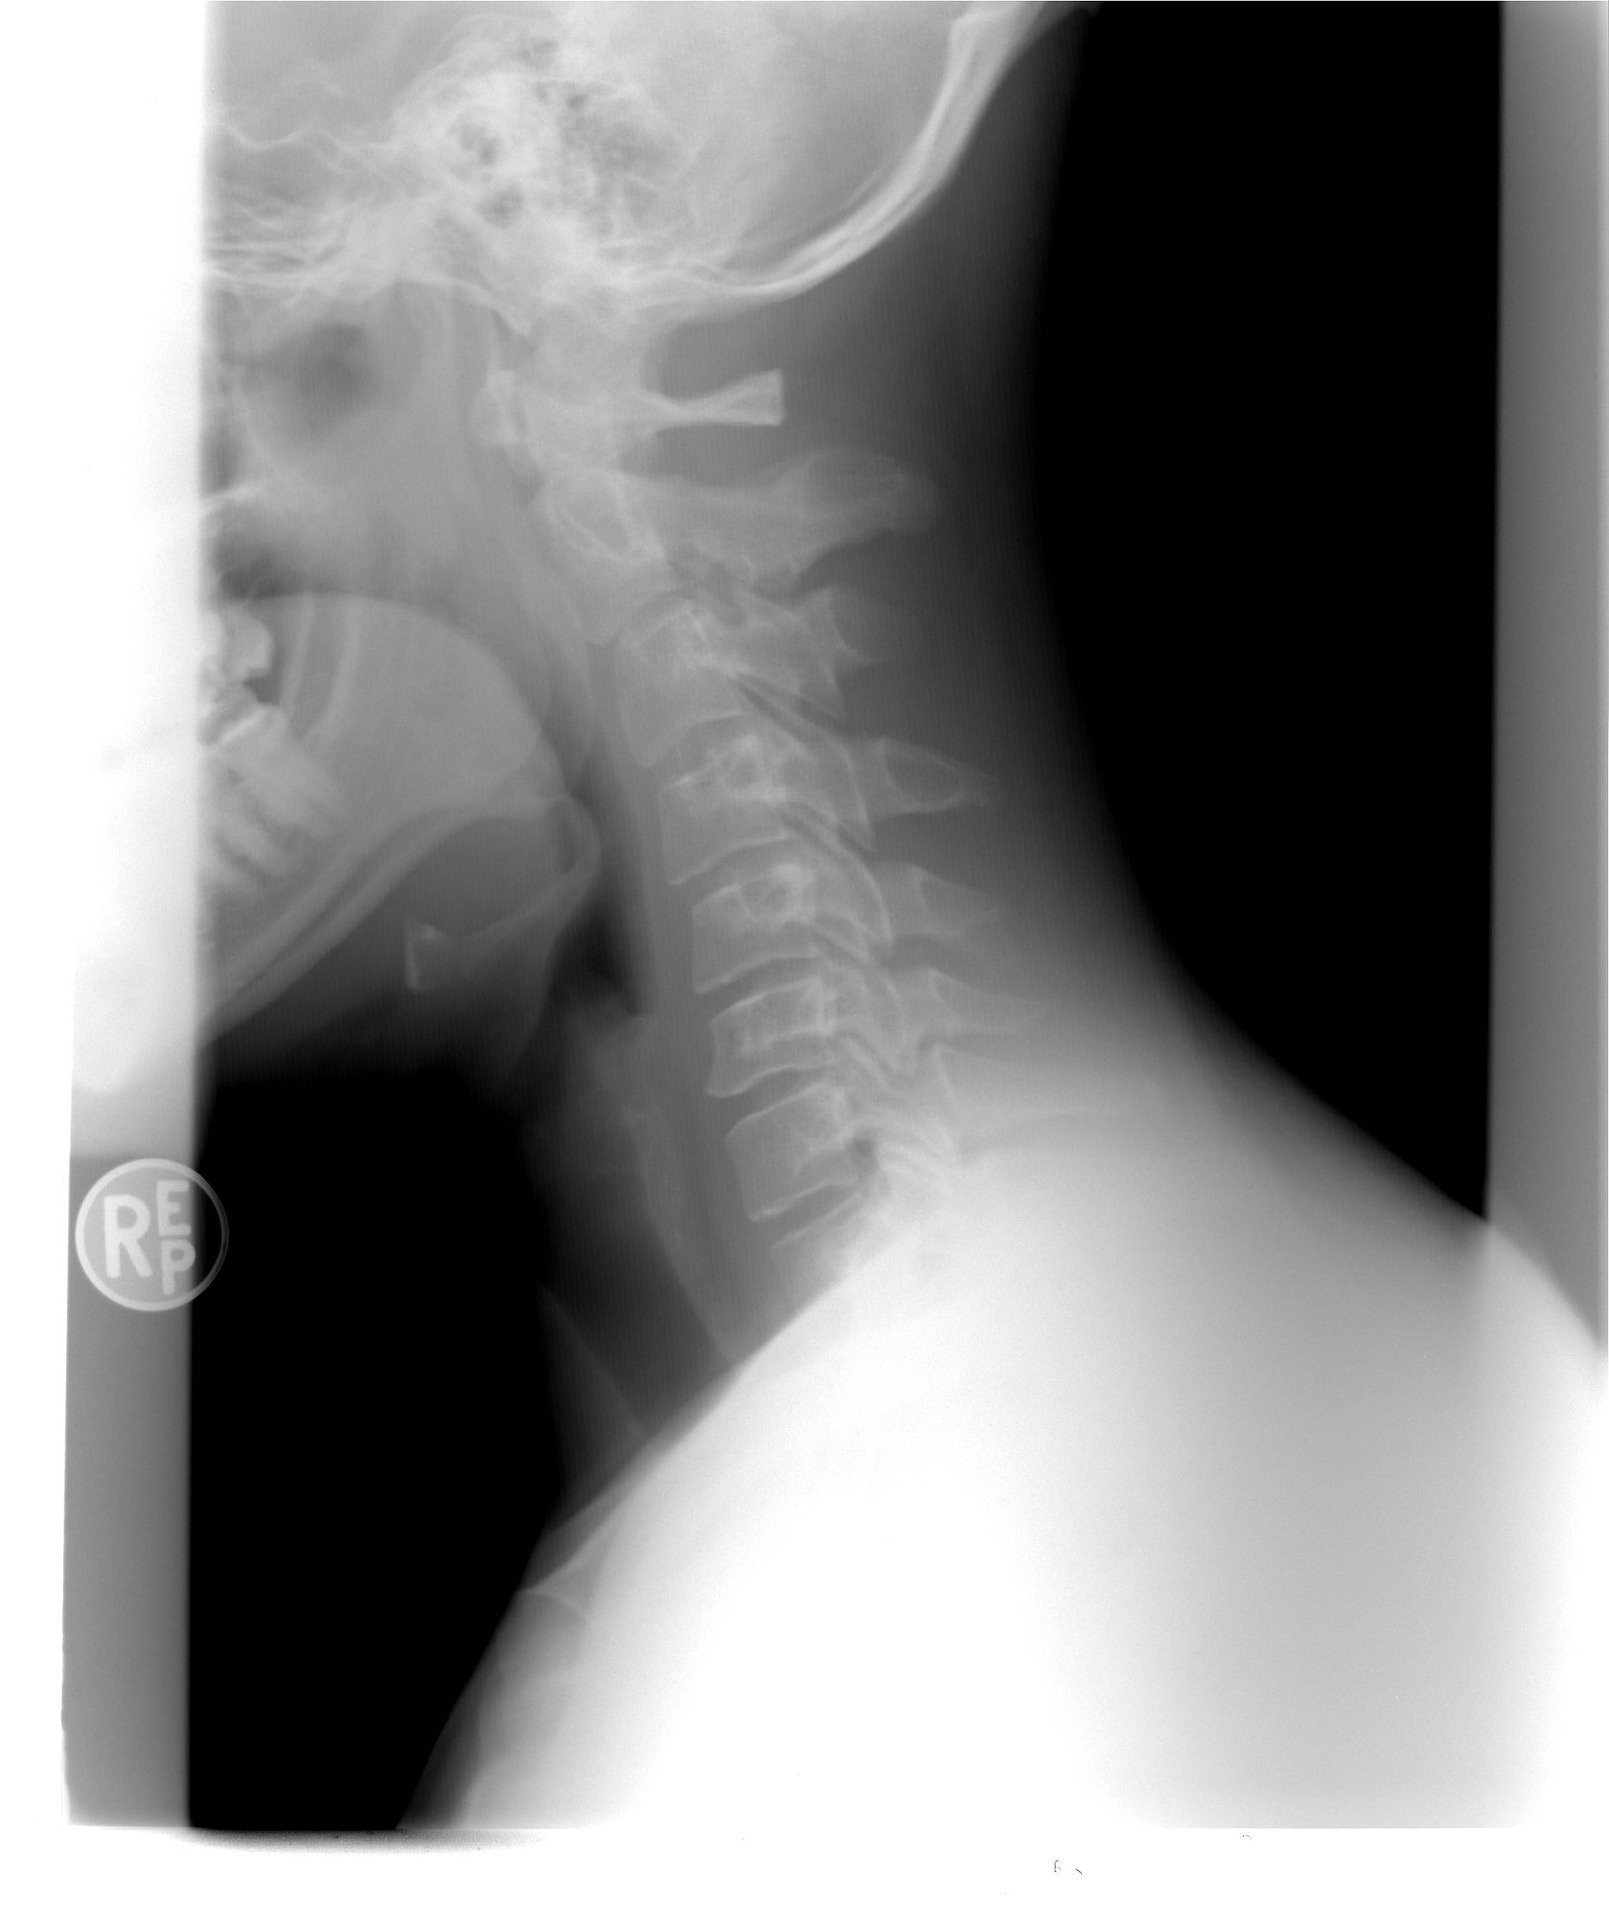

从医学角度讲,颈椎的生理前曲是脊柱生理弯曲重要的组成部分,许多潜在危害都是从颈椎前曲减少开始的。睡眠时间是身体的恢复、放松期,只有充分、恰当、适度地保持颈椎前曲,才能够使颈椎得到充分的休息与恢复。所以选对枕头的第一要务就是能够维持颈椎正常的生理曲度。